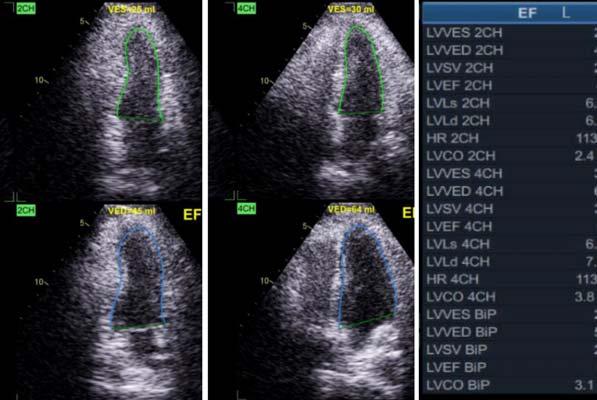

All patients underwent 2D-TTE before coronary angiogram and PCI. The LV ejection fraction was assessed by Simpson’s biplane method, and GLS was estimated by speckle-tracking echocardiography. The following Echocardiographic parameters were also analysed: End Diastolic Volume, End Systolic Volume, Stroke Volume, Mitral Regurgitation.

The mean LV ejection fraction were 46.54±8.8%, 47.9±8.6% and 51.12±7.6% at preprocedural, at 3 months follow-up and at 6 months follow-up respectively. The mean increase in Left Ventricular Ejection Fraction (LVEF) was 1.3% at 3 months follow up and 4.6% at 6 months follow-up. The mean Global Longitudinal Strain (GLS) were -11.5±3.3, -13.2±4.9 and -15.1±3.1 at preprocedural, at 3 months follow-up and at 6 months follow-up respectively. The mean increase in GLS was -1.66 at 3 months follow up and -3.6 at 6 months follow-up from baseline.

Mean Left Ventricular End-Diastolic Volume (LV EDV) were 83.6±12.1 ml, 86.42±10.8 ml and 88.12±9.9 ml at preprocedural, at 3 months follow-up and at 6 months follow-up respectively. Mean Left Ventricular End Systolic Volume (LVESV) were 44.3±9.4 ml, 44.91±9.9 ml and 42.8±8.4 ml at preprocedural, at 3 months follow-up and at 6 months follow-up respectively. Mean LV SV were 39±9.7 ml, 41.4±8.9 ml and 44.6±7.9 ml at preprocedural, at 3 months follow-up and at 6 months follow-up respectively.

Paired T-test was used to correlate these values at baseline, 3 months and at 6 months follow-up. EDV and SV were found to increase linearly with time following intervention which was found to be significant with p-value <0.01. ESV was found to decrease at 6 months with a significant p-value <0.05 which may be due to more increase in SV than the simultaneous lesser increase in EDV, suggesting improvement in LV function.

Variable Pre-procedure3 Months6 Months P-value LVEF46.54±8.847.88±8.651.12±7.6<0.01 GLS-11.53±3.3 -13.2±4.86-15.05±3.1<0.01

Table 2 — Comparison of Echo Parameters at Baseline, at 3 Months and at 6 Months

Variable Pre-procedure3 Months P-value6 MonthsP-value EDV83.6±12.1 86.42±10.8 <0.0188.12±9.9 <0.01 ESV44.29±9.444.91±9.90.22742.77±8.3<0.05 SV39±9.6941.35±8.9 <0.0144.60±7.9 <0.01